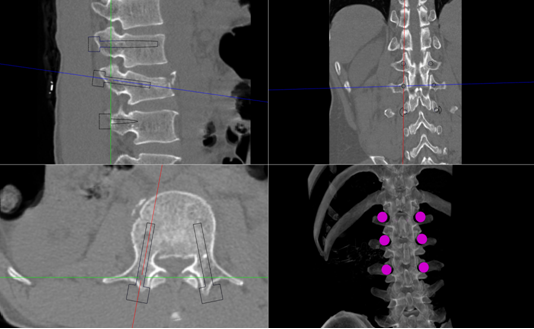

在刘时璋主任精心筹备、悉心安排下,术前手术医生团队和手术机器人技术保障团队密切协作,详细分析了患者腰椎CT资料,精确规划了椎弓根螺钉通道位置及各项参数,重建模拟椎弓根螺钉植入后三维图像,并不断优化方案使其更精准、安全,并进行了手术机器人使用的术前演练。手术当天,常彦海主任医师和陈明副主任医师共同为患者实施了手术。术中,借助C臂获取患者腰椎正侧位影像及标记定位,将其传入机器人系统与患者术前腰椎CT质料匹配映射,确定了每个螺钉的实际穿刺通道,通过机械臂在压力监测和光学追踪引导下依次钻入导针,最后精准植入6枚椎弓根螺钉。脊柱周围毗邻重要神经和血管,椎弓根螺钉通道空间有限,常规经皮植钉技术风险大,容易发生神经损伤等并发症,且术中需要反复透视,手术机器人很好弥补了这些弊端,相当医生有了“透视眼”和“第三只手”,使手术操作更加智能化、精准化。